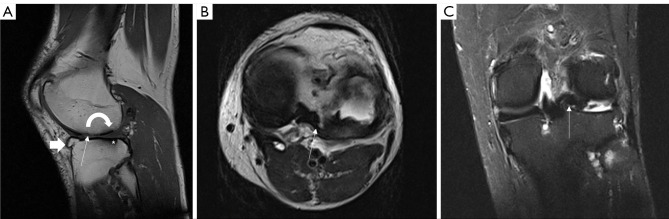

Abstract Image